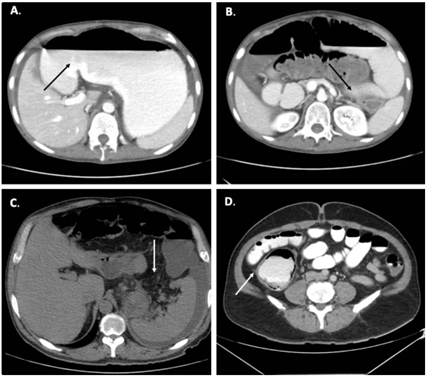

En la Figura 2 se muestran algunos ejemplos de los posibles hallazgos en la tomografía abdominal. La identificación en la TC de una zona de transición es de vital importancia como un indicador de manejo quirúrgico, asociado a una ingurgitación de venas mesentéricas, el espesor de la pared intestinal mayor de 3 mm, la presencia de neumatosis intestinal, el edema mesentérico, el líquido libre intraabdominal y el gas en la vena mesentérica o porta, entre otros 10,11. Estos signos imagenológicos se resumen en la Figura 3.